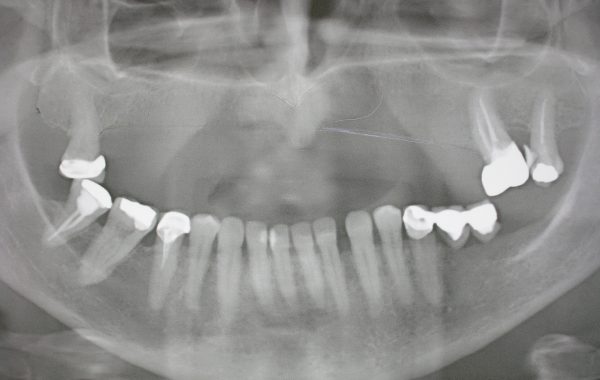

Ahora presentaremos las radiografías de una paciente de 55 años donde se aprecia la falta de hueso por debajo de los senos maxilares debido a la ausencia de los dientes, como mencionamos este proceso de pérdida de hueso es normal y no es patológico. Después apreciamos la radiografía donde se hace el procedimiento de elevación de seno maxilar donde se aprecia la colocación del injerto con los implantes ya colocados.

Aquí se observa la poca cantidad de hueso por debajo de los senos maxilares